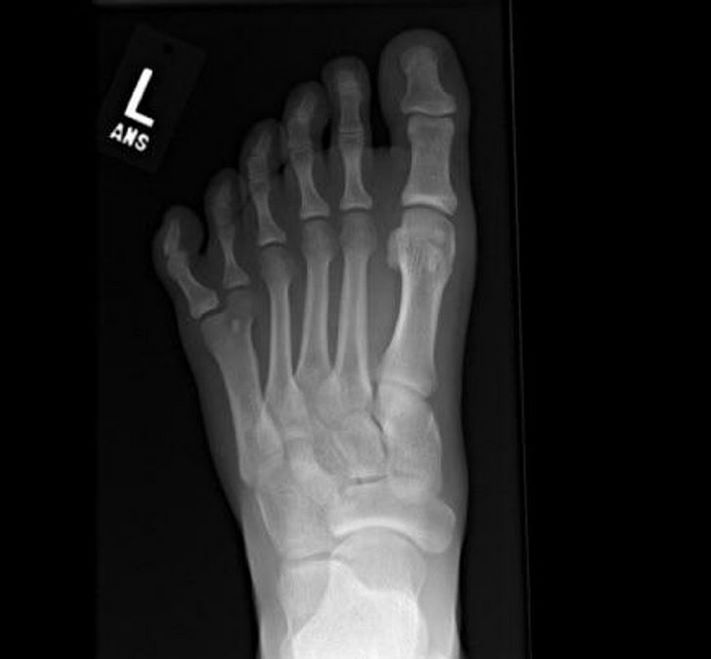

Ոտնաթաթ` անսովոր թվով մատներով